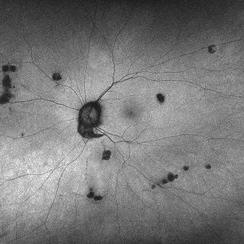

Autofluorescence image of a 63-year-old woman with presumed ocular histoplasmosis syndrome OD observed for change.

Photographer: Cathy Harsma, COA

Condition/keywords: histoplasmosis, presumed ocular histoplasmosis syndrome (POHS)